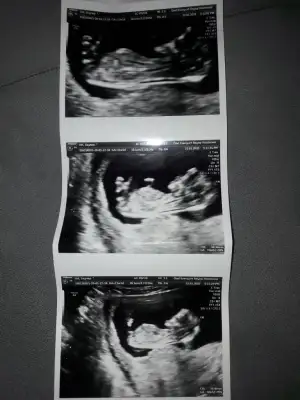

Bana da tahmin yapar mısın canım

Eklentiler

• 20200114_132625.webp

20200114_132625.webp

14,1 KB · Görüntüleme: 67